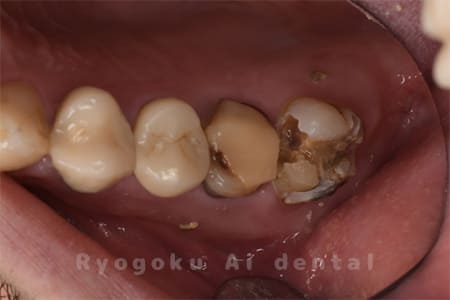

Case12

-

- 原因

- 縁下カリエス

- 治療内容

- クラウンレングスニング、ジルコニアクラウン修復

- 治療費用

- 約220,000円

被せ物の中から臭いがするとのことで、被せ物を外したところ大きな虫歯となっていました。このまま被せてしまうと被せ物が外れやすいため、埋まっている歯を出すためのクラウンレングスニング処置を行い、その後、ジルコニアクラウンで被せ物を行いました。